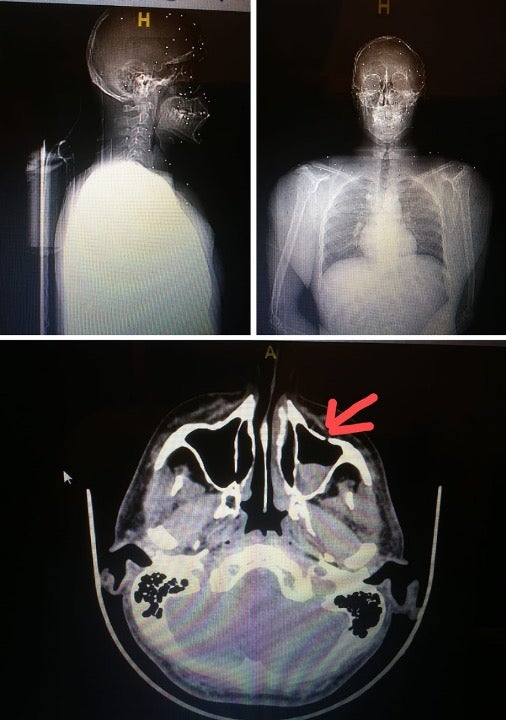

أصابت عشرات كريات الخردق هذا المتظاهر بثقب في فروة رأسه واستقرت تحت جيوبه الأنفية وفي عينه.